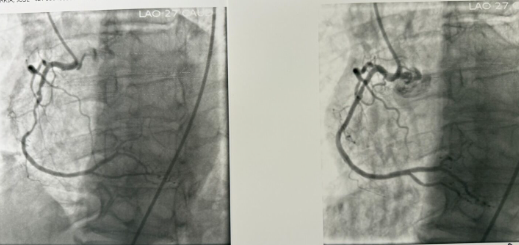

Percutaneous Coronary Intervention (PCI)

Stent placement after balloon angioplasty widens a narrowed coronary artery.

A coronary stent helps keep the artery open and restore healthy blood flow